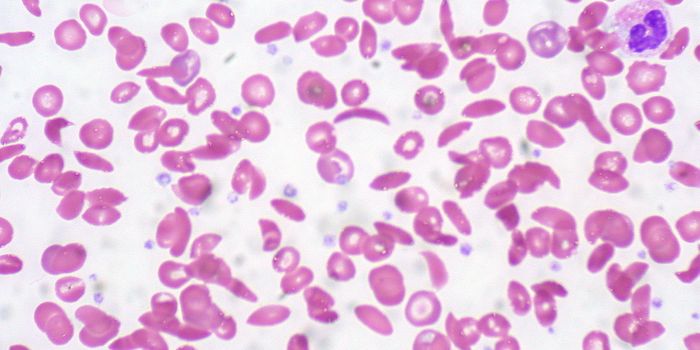

AUG 10, 2016CardiologyCardiovascular problems are among the top causes of death in people with sickle cell anemia, a genetic disease caused by ...

FEB 11, 2016CardiologyRare but deadly, thrombotic thrombocytopenic purpura (TTP) is a disease where blood clots block the smallest blood vesse ...